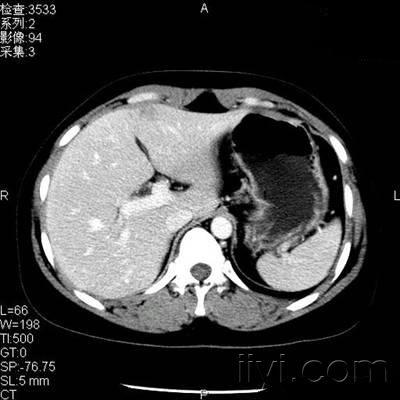

患者,女性,体检发现肝左叶低密度病变2天

延迟5分钟